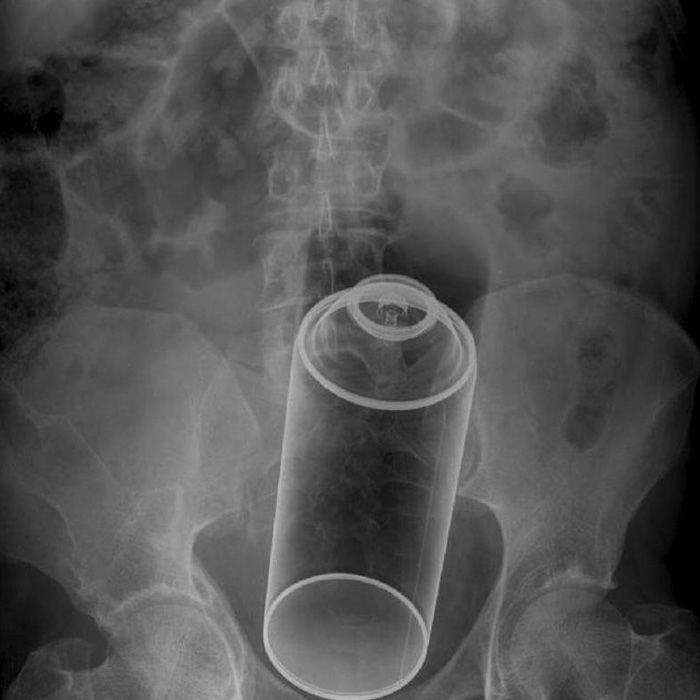

▼這個就是身體裡塞個一個罐子

圖片來自:ems1